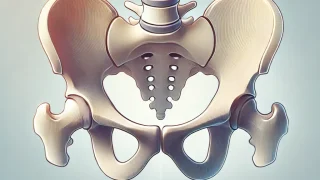

人体の基本マニュアル 骨盤を締める筋肉や骨膜のリスト

骨盤プロジェクト - 骨盤を締める働きをする筋肉と支持構造 梨状筋(Piriformis muscle): 骨盤を安定させる深層筋で、骨盤内と外側の調和を図る。 多裂筋(Multifidus muscle): 骨盤と脊柱をつなぎ、骨盤を引き...